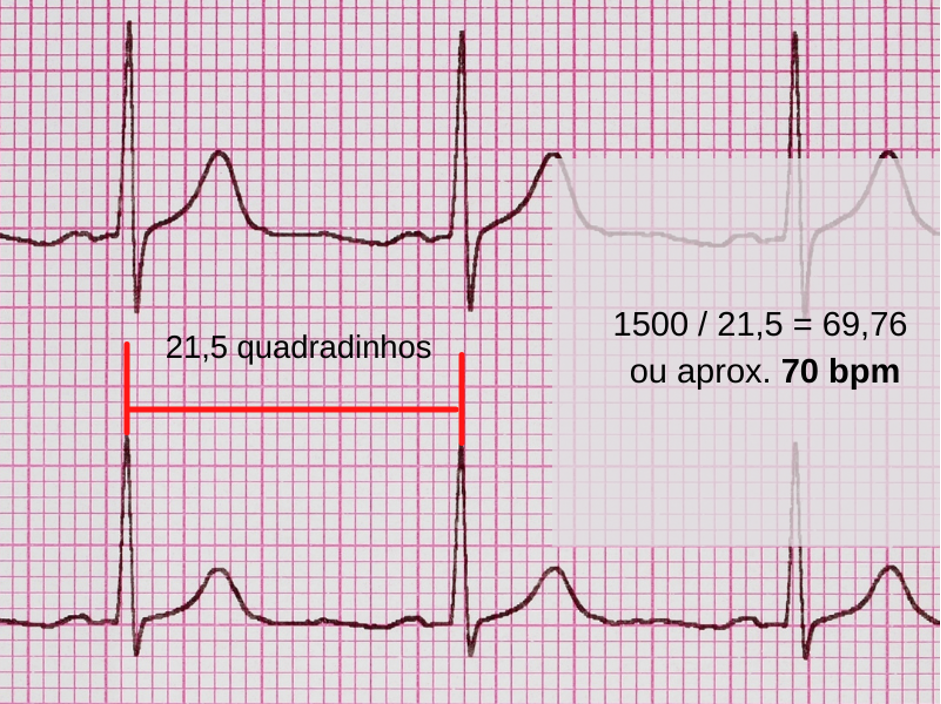

Figura 3: Regra do “1500 dividido pelo número de quadradinhos”.

E por que fazemos essa conta? Porque estamos contando quantos batimentos com o intervalo de 21,5 quadradinhos cabem em 1500 quadradinhos (ou um minuto). Lembrando que o primeiro batimento, o da esquerda na foto, entra como base de início para o cálculo, ou seja, em 21,5 quadradinhos aparece o primeiro batimento exatamente após o término do anterior.

É importante lembrar que esse cálculo só é válido para ritmos regulares, ou seja, aqueles em que o intervalo RR se mantém constante. Caso isso não ocorra, como numa fibrilação atrial por exemplo, não vai ser possível estimar a FC por este método e vamos precisar lançar mão de outra maneira – fique tranquilo, vamos ver mais pra frente.